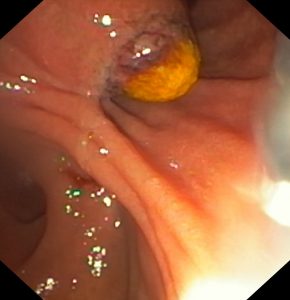

BVXA-VL: MẮC MỘT LƯỢT 3 MẢNH XƯƠNG CÁ LÓC SẮC NHỌN ĐÂM THÀNH THỰC QUẢN

Bệnh viện Xuyên Á Vĩnh Long vừa tiếp nhận Cấp Cứu gắp dị vật thành công cho Bệnh nhân V.V.C (57 tuổi, ngụ tại xã Thạnh Hải, tỉnh Bến Tre), bị hóc xương cá trong lúc đang ăn cơm chiều. Ngay sau khi hóc xương bệnh nhân có biểu hiện nuốt vướng, khó chịu, đau rát họng nên nhanh chóng vào Cấp Cứu Bệnh viện Xuyên Á Vĩnh Long để được xử trí.